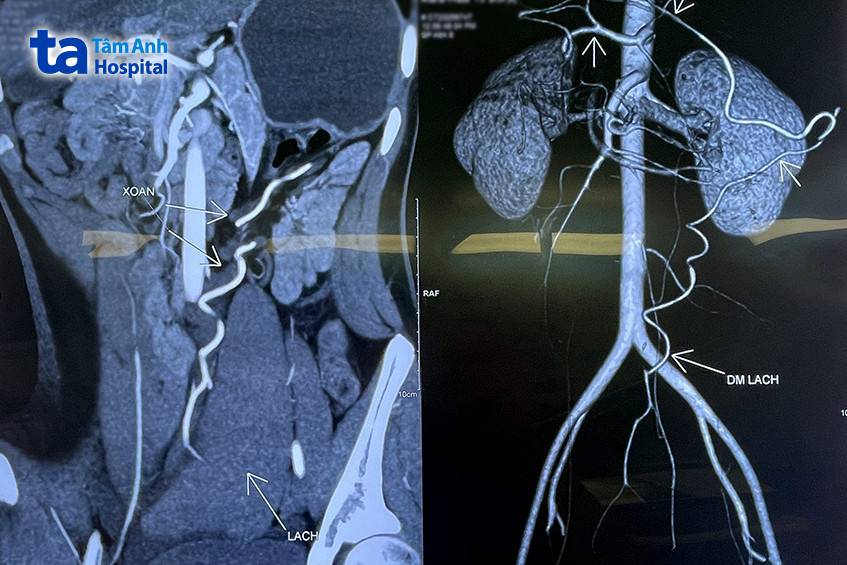

Em Thu Hà (Nam Định) thăm khám tại Bệnh viện Đa khoa Tâm Anh Hà Nội vào ngày 20/7 do đau bụng âm ỉ tăng dần kèm nôn. Trước đó em đã đi khám tại nhiều cơ sở y tế trong 4 ngày nhưng không tìm ra bệnh. Bác sĩ khoa Ngoại tổng hợp hỏi kỹ bệnh sử và khám vùng hố chậu trái và hạ vị có khối kích thước khoảng 8 cm, bờ rõ, mật độ chắc, di động được, ấn đau nhói. Qua siêu âm và cắt lớp vi tính thấy lách lạc chỗ nằm ở tiểu khung, có thâm nhiễm mỡ và nhiều dịch vùng tiểu khung. Bác sĩ kết luận em bị xoắn lá lách khả năng chưa có hoại tử. Hình ảnh lách to phù nề do ứ máu nhưng còn tưới máu.

PGS.TS.BS Triệu Triều Dương, Giám đốc khối Ngoại, BVĐK Tâm Anh Hà Nội cho biết, ngay khi tiếp nhận và chẩn đoán bệnh, bác sĩ tiến hành phẫu thuật nội soi cấp cứu lúc 19h cùng ngày. Quá trình phẫu thuật bác sĩ quan sát thấy lách to, kích thước khoảng 15 x 10 cm, màu tím, ứ máu, sa xuống vùng hố chậu trái và tiểu khung, được mạc nối lớn phủ lên. Cuống lách dài bị kéo căng, tĩnh mạch lách giãn to, xoắn bán phần. Bệnh nhân được tháo xoắn gỡ dính lách khỏi các dây chằng xung quanh và mạc nối lớn. Bác sĩ tạo hình túi bằng 2 tấm lưới nhân tạo, cho lách vào túi, khâu treo cố định lách về vị trí giải phẫu bình thường, đặt dẫn lưu và đóng vết mổ.